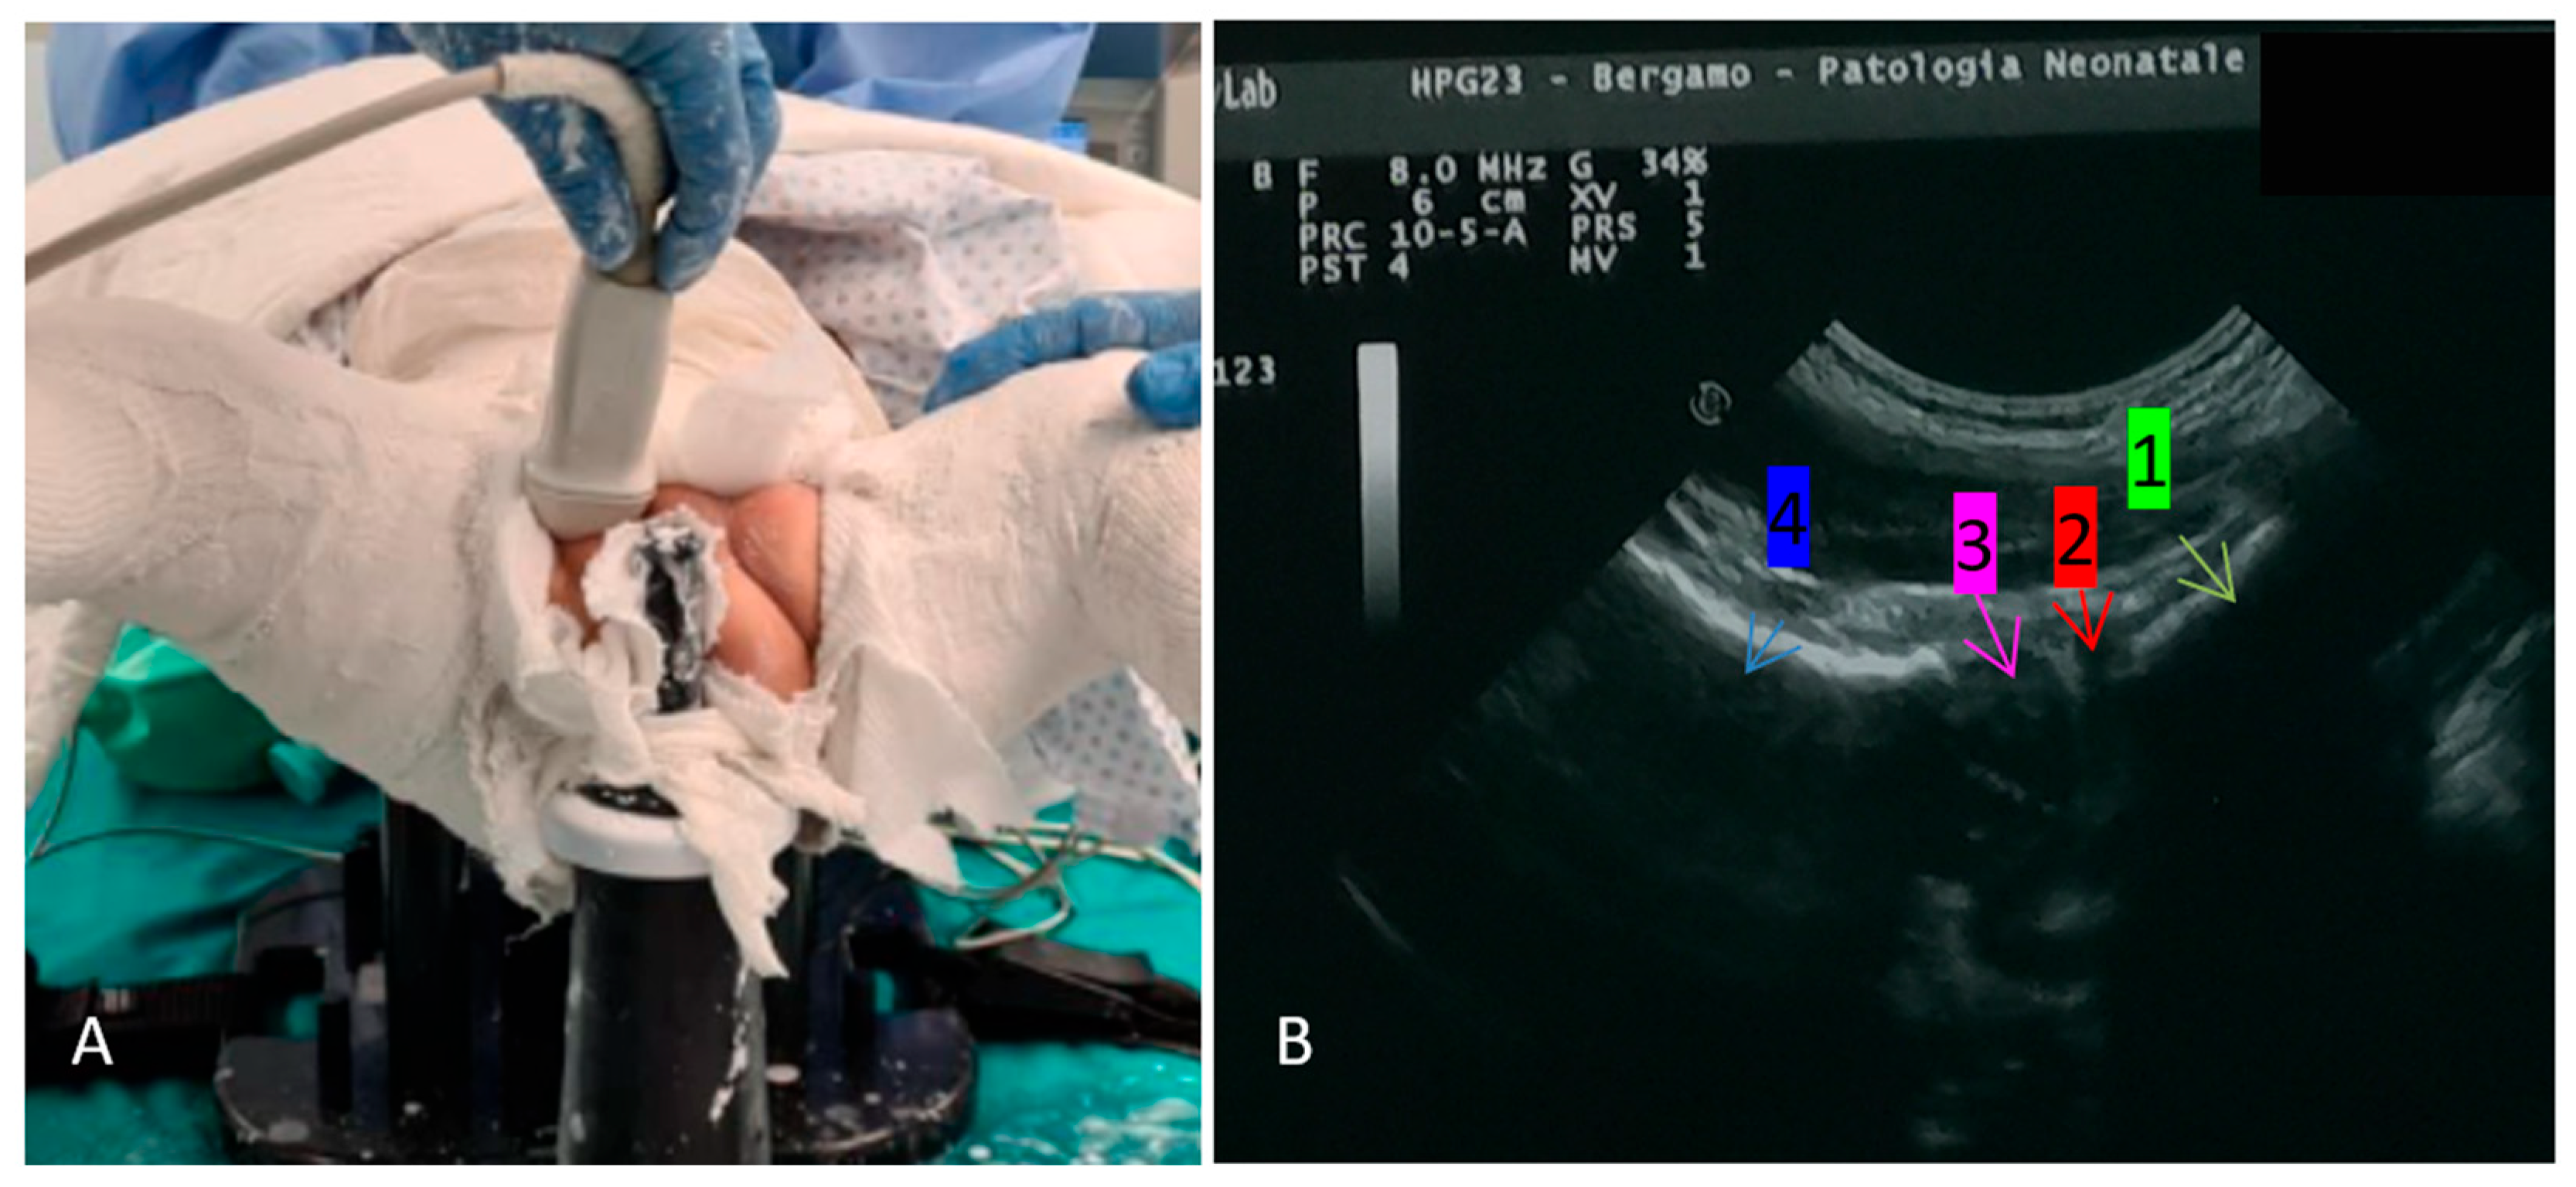

2. Materials and Methods